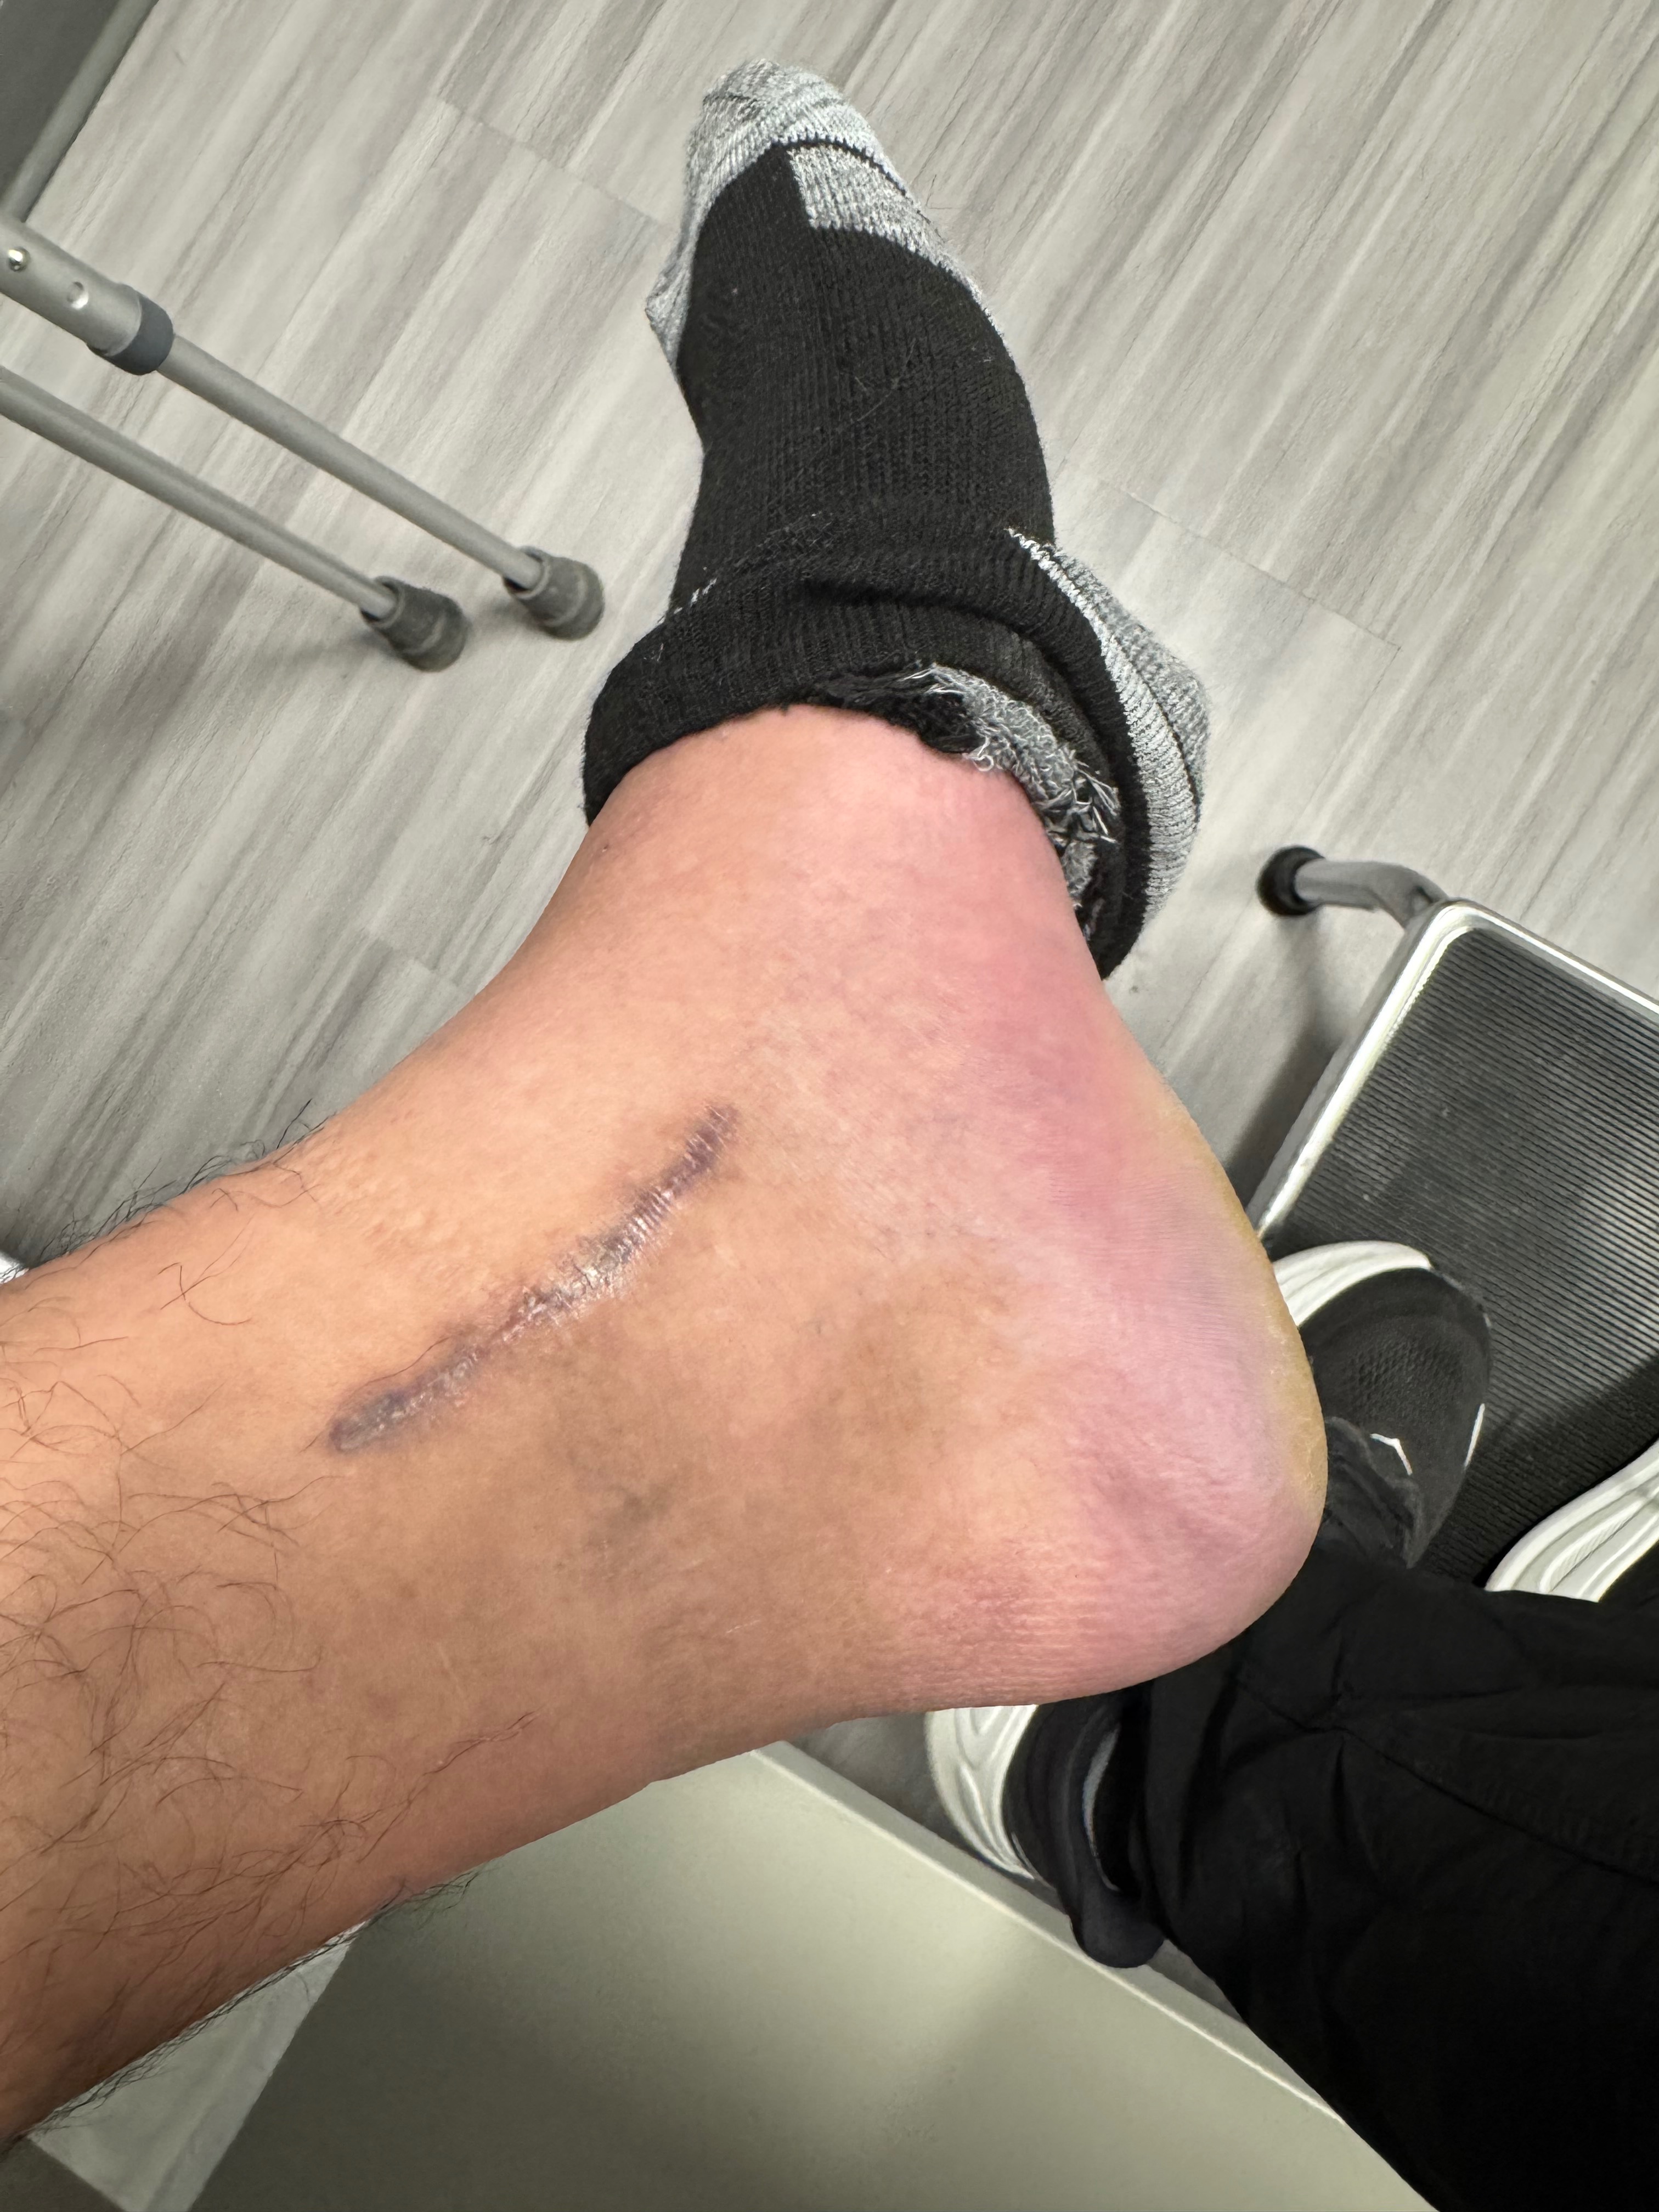

En mayo de 2025, mientras trabajaba, un elevador de tijera de 3,200 libras se descontroló y pasó por encima de mi tobillo, aplastando y destrozando la parte baja de mi pierna. Ese día no solo se rompieron mis huesos, también se quebró mi independencia, mis sueños y la vida que conocía.

Sufrí fracturas múltiples, hemorragias internas y un daño nervioso tan severo que los médicos me diagnosticaron CRPS (Síndrome de Dolor Regional Complejo) — conocido como “la enfermedad más dolorosa del mundo”.

Hoy vivo atrapado en un cuerpo que ya no responde como antes. Un simple roce se siente como fuego. Una brisa ligera me atraviesa como cuchillas. No puedo vestirme solo, no puedo caminar sin agonía, y hasta dormir se ha vuelto un lujo que rara vez consigo.

In May 2025, while working, a 3,200-pound scissor lift went out of control and rolled over my ankle, crushing and destroying the lower part of my leg. That day, not only were my bones broken, but also my independence, my dreams, and the life I once knew.

I suffered multiple fractures, internal bleeding, and severe nerve damage that led doctors to diagnose me with CRPS (Complex Regional Pain Syndrome) — known as “the most painful disease in the world.”

Now I live trapped in a body that no longer responds the way it used to. A simple touch feels like fire. A light breeze feels like knives cutting into me. I cannot dress myself, I cannot walk without unbearable agony, and even sleeping has become almost impossible.